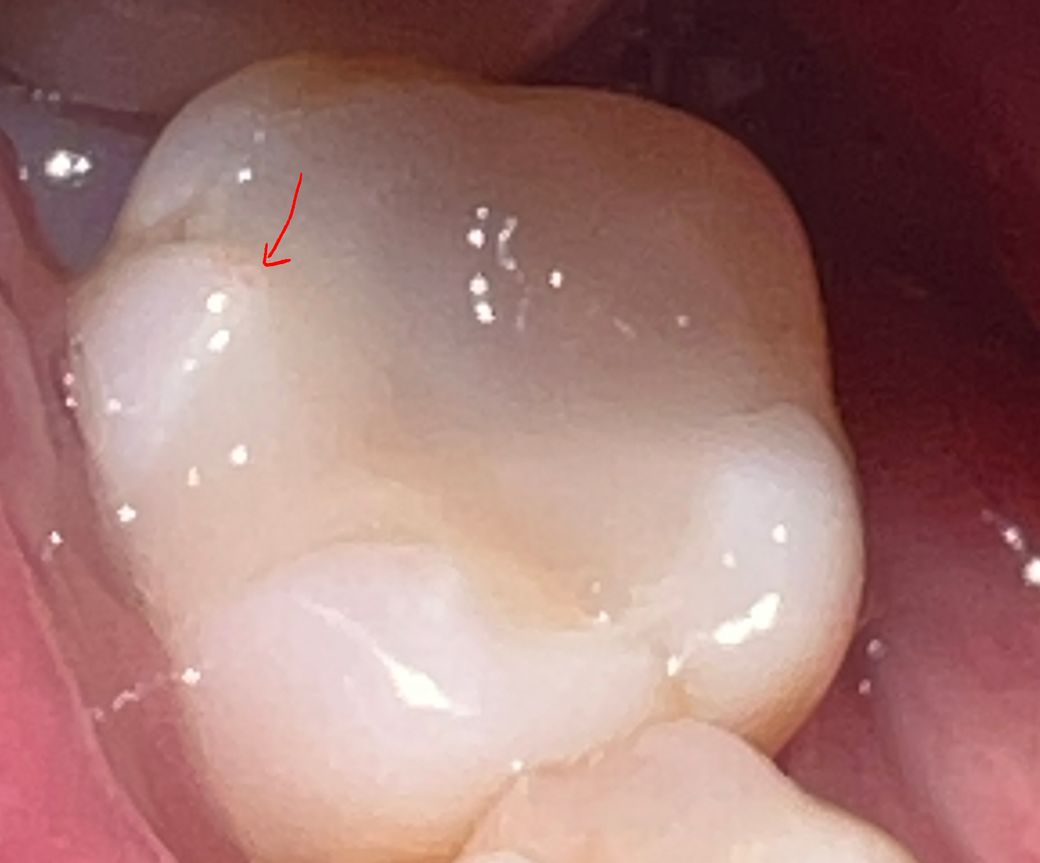

인레이가 깨지고 치아에 구멍이 난 것처럼 보이는데요

화살표친 부분은 인레이가 아닌 치아 부분인데 마치 구멍난 것처럼 보이네요.

그 옆은 깨져있구요.

구멍난 것처럼 보이는 부분도 인레이가 있던 자리일까요? 뽀쬭한 부분이라 인레이가 있던 자리 같지가 않아서요.

화살표 한곳은 치아가 마모되면서 구멍이 생긴거라 특별히 치료를 하지 않으셔도 됩니다. 하지만 인레이가 깨진부위가잇다면 다시 하시는게 좋을수도 있습니다.

인레이의 경계부위가 깨지게 되면 구멍이 난것처럼 보일수도 있습니다.